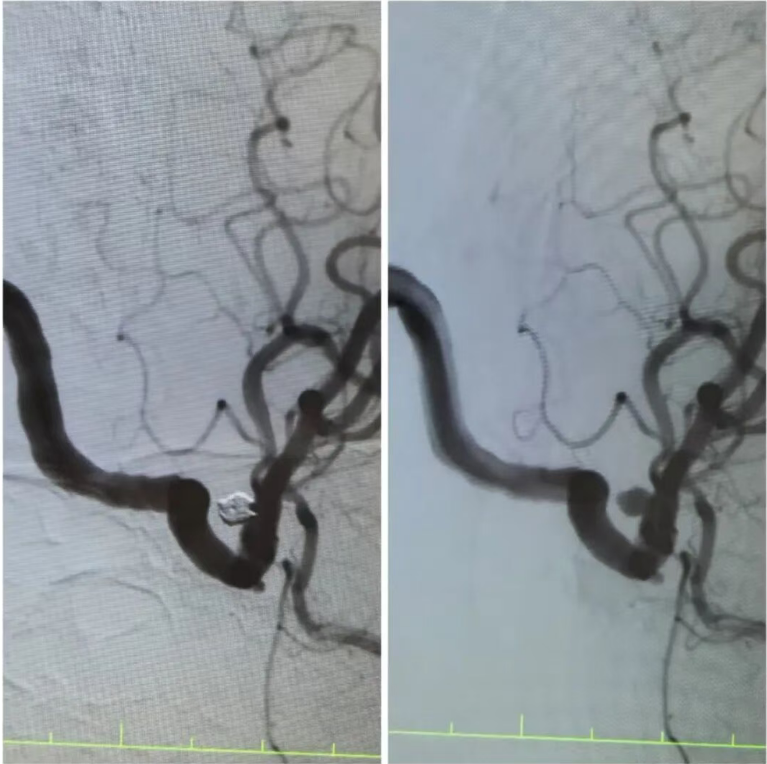

在王阿姨的造影檢查上,可清晰地看到動(dòng)脈瘤的形態(tài):如同血管上懸掛的“小囊袋”,薄如蟬翼的瘤壁隨時(shí)可能再次破裂?!伴_(kāi)顱手術(shù)創(chuàng)傷大,老人基礎(chǔ)疾病多,風(fēng)險(xiǎn)極高,而介入栓塞術(shù),能通過(guò)股動(dòng)脈穿刺的“鑰匙孔”路徑,精準(zhǔn)封堵動(dòng)脈瘤。”手術(shù)團(tuán)隊(duì)反復(fù)推演方案,最終選定顱內(nèi)動(dòng)脈瘤栓塞術(shù)——用纖細(xì)的微導(dǎo)管將彈簧圈送入動(dòng)脈瘤腔內(nèi),像“織網(wǎng)”一樣填充瘤腔,隔絕血流沖擊,從根源上消除破裂風(fēng)險(xiǎn)。

手術(shù)臺(tái)上,丁院長(zhǎng)握著導(dǎo)管在血管中精準(zhǔn)穿梭,如同在迷宮中尋找唯一的出口。當(dāng)微彈簧圈依次填入動(dòng)脈瘤,造影顯示瘤腔被完美“封堵”,載瘤動(dòng)脈血流恢復(fù)通暢,這枚困擾老人許久的“炸彈”,終于被安全拆除。術(shù)后的王阿姨頭暈頭痛癥狀消失,胸悶氣短的老毛病也因身心狀態(tài)改善而減輕?!案杏X(jué)腦袋里的‘炸彈’沒(méi)了,整個(gè)人都輕快了!”